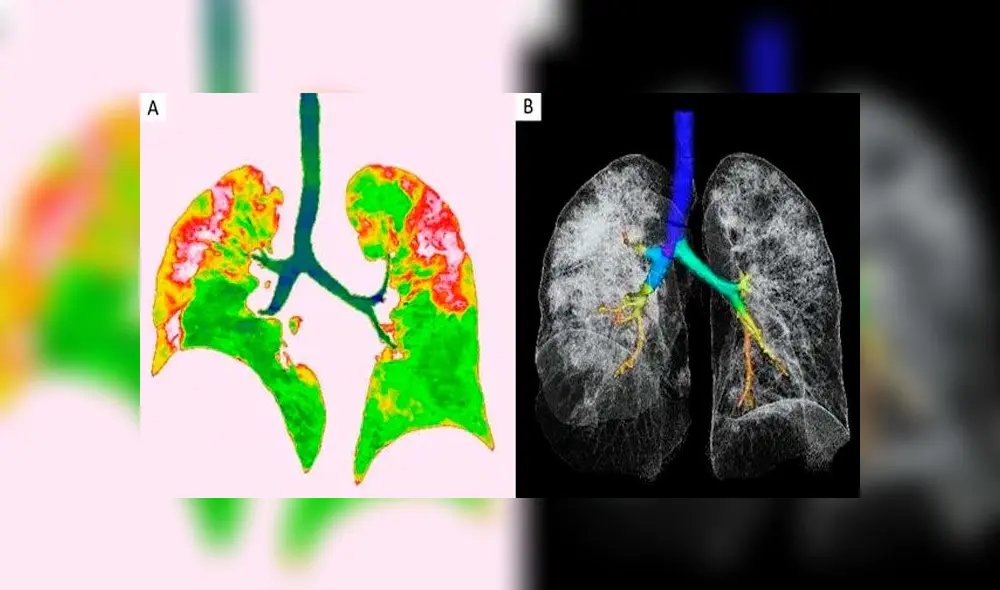

El daño provocado por el nuevo coronavirus en los pulmones de las personas infectadas es graficado en una serie de tomografías realizadas a víctimas del COVID-19 en China. Las imágenes fueron difundidas recientemente por la Sociedad Radiológica de América del Norte.

En un grupo de placas se observa la evolución de los pulmones de un hombre de 44 años, procedente de China, quien trabajaba en el mercado de mariscos de Wuhan, donde se cree que surgió el brote. Las tomografías muestran unas manchas blancas en las esquinas inferiores de dichos órganos, conocidas por los radiólogos como “opacidad de vidrio esmerilado”.

Estas anomalías indican un llenado parcial de espacios de aire en los pulmones, de forma parecida a lo registrado en pacientes con enfermedades como el SARS y el MERS.

El hombre ingresó al hospital el 25 de diciembre pasado tras experimentar fiebre y tos por unas dos semanas, siendo diagnosticado con neumonía y síndrome de dificultad respiratoria aguda. Los escaneos grafican como, a medida que pasa el tiempo, el líquido en los mencionados espacios se hace más pronunciado.

Una semana después de su hospitalización, el individuo falleció.

Otro conjunto de imágenes computarizadas muestra el mismo llenado de espacios de aire en los pulmones de una mujer de 54 años, quien se infectó con coronavirus tras un viaje a Wuhan. Ella experimentó fatiga, tos, fiebre y congestión en el pecho, siendo luego diagnosticada con neumonía severa ocasionada por el COVID-19.